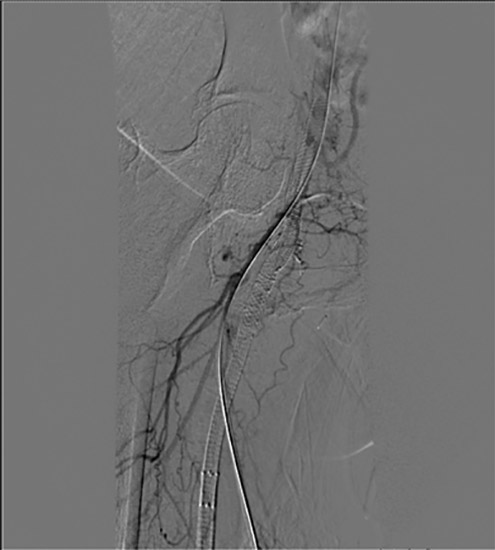

Figure 5. Baseline angiogram showing R CFA occluded stent jailing occluded profunda

Figure 6. Retrograde crossing from right profunda artery to the right external iliac artery

An angiogram showed patent abdominal aorta, bilateral common iliac arteries with existing stent, and occluded bilateral internal iliac arteries. The distal right external iliac artery had 60% stenosis. The left external iliac artery was patent. The right common femoral artery had an occluded stent jailing a known ostial CTO of the right profunda femoral artery, which filled poorly via collaterals. The right superficial artery was occluded.

We gained left femoral artery access with up-and-over technique sheath advance to the right external iliac artery. As expected, we failed to cross the right CFA occluded stent to the jailed right profunda. Ultrasound access was obtained in the right profunda femoral artery in a retrograde fashion. We probed the chronic total occlusion of the ostial segment of the right profunda and the CFA in retrograde fashion, but we could not get into the true lumen of the right external iliac. We then used the IVUS guided crossing device, “Pioneer,” and successfully crossed the occlusion of the right common femoral artery. The entire crossing passage was outside the existing occluded CFA stent and inside the wall of the CFA. The lesion was pre-dilated with a 5×20 mm PTA balloon and then a 6×40 mm PTA balloon. Despite the good release of the lesion at 10 atm, there was severe recoil post dilation of 80% residual stenosis. We inserted a 7×80 mm Zilver PTX DES stent into the right common femoral artery, followed by a balloon expandable short stent at the iliofemoral junction for persistent recoil.

The completion angiogram showed excellent results, with the initial 100% chronic total occlusion of the common femoral artery and profunda femoral vessels reduced to under 30%, and the terminal right external iliac 60% reduced to less than 30%. The entire new stent was deployed in double-barrel fashion alongside the occluded R CFA old stent.  The patient healed her nonhealing right AKA stump wound within three months post intervention. Eighteen months later, recurrent vague stump pain with suboptimal arterial duplex US led to another angiogram (Figure 8) that confirmed continued patency.